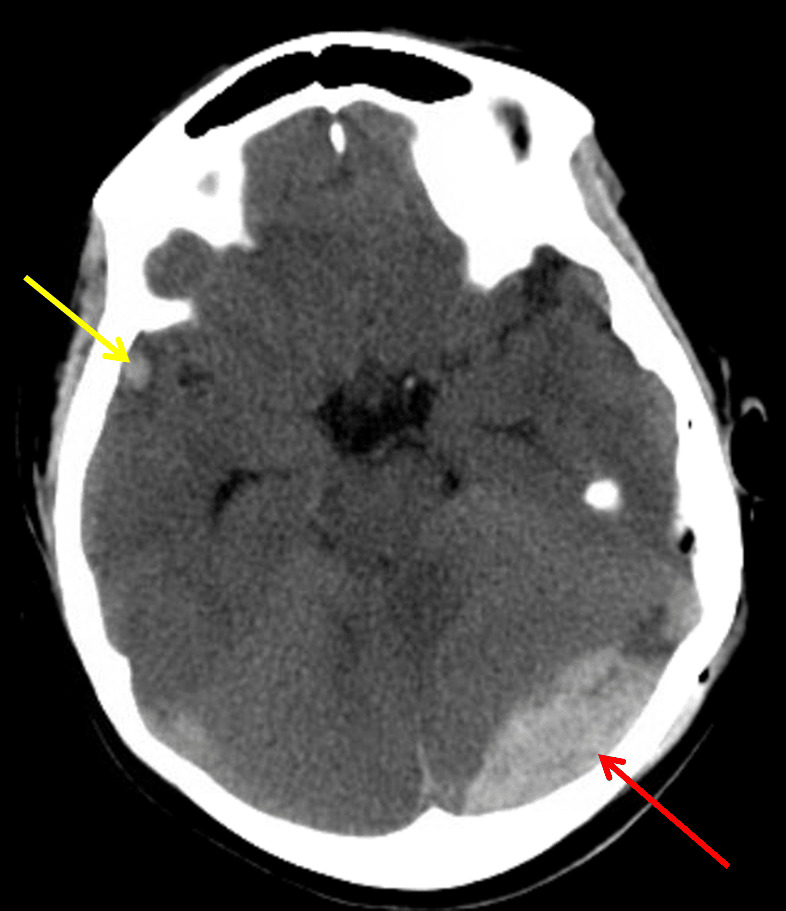

Red arrow: acute epidural hematoma. Yellow arrow: small contrecoup cerebral contusion.